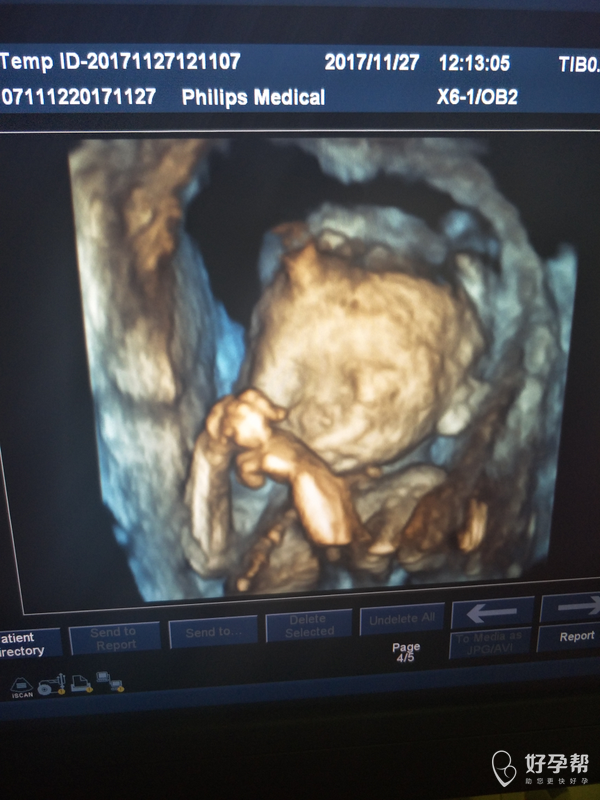

做的四维彩超,医生说有点偏小,不知道是不是严重偏小了,医生说没有明显畸形,其他的也没有仔细问医生,麻烦各位医生看看宝宝有没有严重偏小,有没有脐带绕颈。